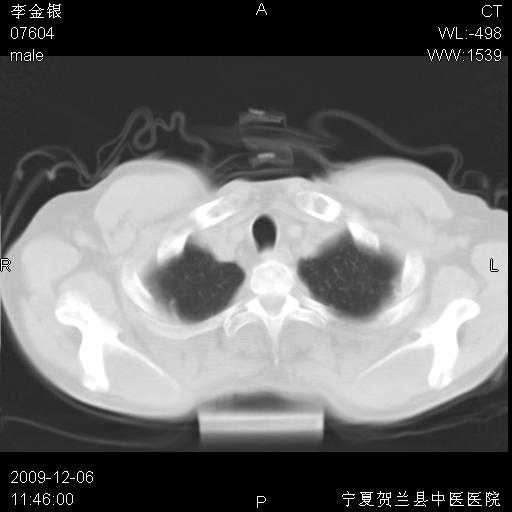

该病人 ,男,62岁,主因咳痰带血两天

考虑右肺中央型占位性病变并阻塞性肺炎.(右肺上叶支气管变窄),建议支纤镜检查.

支气管壁明显增厚 管腔狭窄,腔静脉后多个淋巴肿大,结合年龄病史考虑右肺上叶中央型肺癌并阻塞性肺炎

右肺上叶后段支气管阻塞,右上肺门占位,相应肺段阻塞性肺炎,右肺门有淋巴结肿大。诊断右肺上叶中心型肺癌,阻塞性肺肺炎、右肺门淋巴结转移。

右上叶支气管狭窄,管壁增厚,远端斑片状软组织影,病灶邻近叶间裂,叶间裂无移位。

诊断右肺中央型肺癌。

那个片影应该大部分都是病灶,病灶沿肺段支气管分支生长,后段完全显示不清、闭塞。若为不张应该伴有叶裂的移位,若为炎症应有空气支气管征。